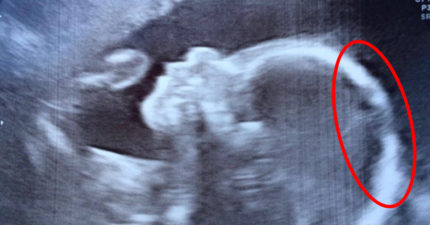

女娃超音波被拍到「過分濃密頭髮」,一出生「滿炸到醫生嚇呆」!(影片)

May 9, 2017